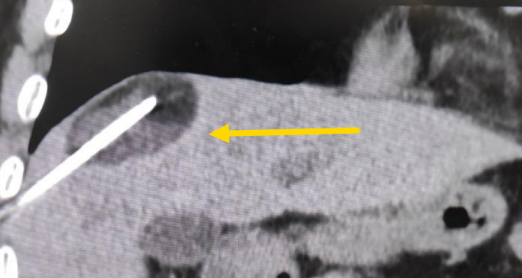

這個患者病變位置刁鉆,穿刺難度大,冷凍消融的難點在于既要不損傷膈肌和肺組織,同時又要盡最大可能完全消融腫瘤。術(shù)前陳寶瑩主任、李鐵柱教授、兀云飛醫(yī)生詳細設(shè)計進針路徑、布針計劃,術(shù)中微創(chuàng)團隊協(xié)調(diào)配合,李鐵柱教授仔細操作,精準到位,順利完成兩個病變的布針,遂啟動治療,先快速降溫到-150多度,再升溫至15?,經(jīng)過兩個循環(huán)反復,即刻觀察到病變完全被冰球覆蓋,同時周圍臟器無損傷,術(shù)中患者幾乎沒有疼痛,還和醫(yī)生聊起了天。

術(shù)中冰球形成